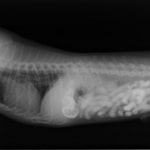

9歳 チワワ 4.8kg

主訴:2日前の夜に桃の種を飲み込んだとのこと。元気・食欲に問題はなく、嘔吐などの消化器症状もみられなかった。誤飲した当日に他院にて催吐処置を試みたが、吐き戻さなかったとのこと。

単純レントゲン検査:明らかな異常所見なし

消化管バリウム造影レントゲン検査:胃内にて異物の存在を疑う異常所見を認めた。

造影直後

内視鏡検査:内視鏡下にて、バスケット鉗子を用いて胃内異物を摘出。

異物内容:桃の種 (約4cm大 写真上)、とうもろこしの芯 (約2.5cm大 写真下)

本症例は、床に落としてしまった桃の種を誤飲していました。動物の体格に対して異物が非常に大きく、開腹手術となる可能性があった症例でした。また、桃の種と一緒に出てきたとうもろこしの芯は、日々のおやつとして与えていたものということでした。とうもろこしの芯は非常に硬く、小さく切って与えても消化されず、長期間胃内に残ってしまうことや腸閉塞の原因となる為、注意が必要です。